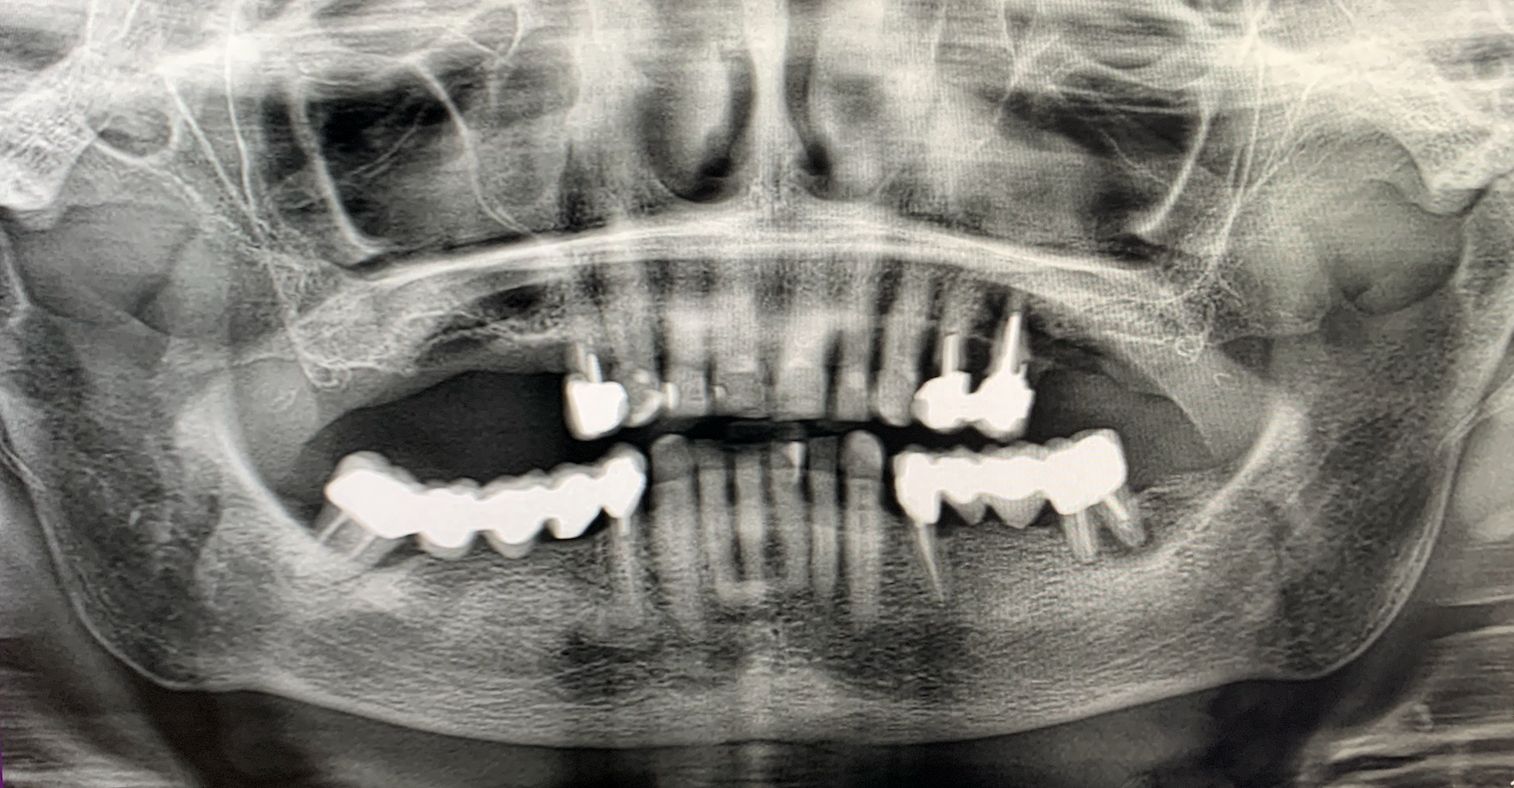

A seguito di un'accurata valutazione clinica e radiografica preparatoria (Fig. 1) è stato pianificato l'inserimento di impianti IS+ (BTK) nelle regioni anteriori e di impianti BT-Rhyno (BTK) nei settori posteriori mediante tecnica transinusale.

Valutazione clinica e radiografica preoperatoria

Fig. 1 - Valutazione clinica e radiografica preoperatoria